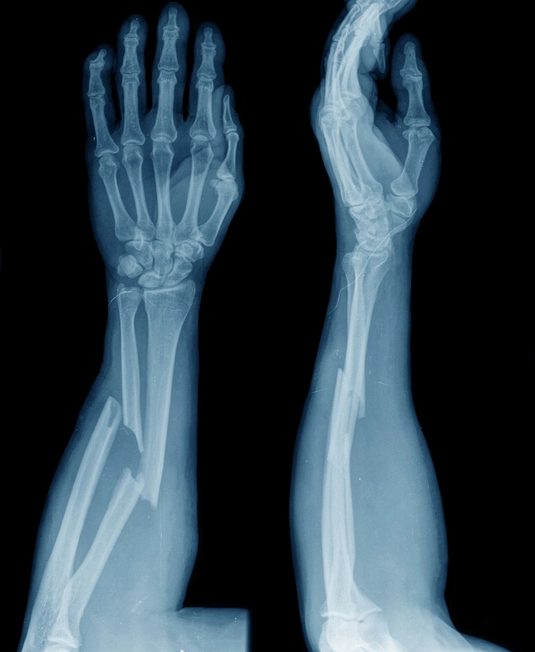

The Most Common Kind Of Armwrestling Injury

For most armwrestlers, spiral fractures of the distal third of the humerus are most common. What the heck is that? Also known as the Holstein-Lewis fracture, this horrifying fracture has your humerus resembling a corkscrew from the twisting motion of your arm. Recovery can take 3-4 months, leaving you out of work and off the table for some time.